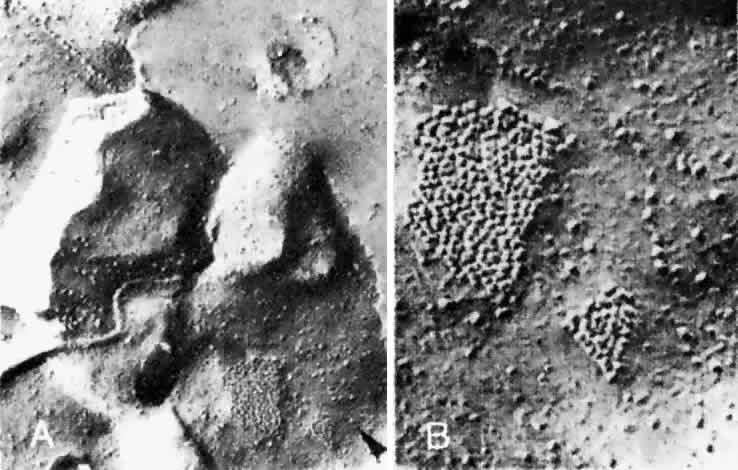

ran in the same plane as the capillaries. Fryczkowski39 introduced the concept of the choroidal functional vascular unit (Fig. 24) to explain the inconsistencies between his anatomic model of the choriocapillaris (lobules

flow from lobule to lobule in the choriocapillaris.  Fig. 24. Choroidal functional vascular unit as proposed by Fryczkowski. A. Anatomical choroidal lobule based on the vascular casts and SEM study. Note

centripetal arrangement of the capillaries. Collecting venule (long, thin arrow) originated from the center of the lobule forming 90° angle with choriocapillaries. B. Functional choroidal lobule outlined by the pressure gradient based on

the fluorescein and ICG angiographic study. Centrifugal arrangement of

the capillaries originated from arteriole. Feeding arteriole reaches

the choriocapillaries at 90° angle. (Courtesy of A. Fryczkowski, MD) Fig. 24. Choroidal functional vascular unit as proposed by Fryczkowski. A. Anatomical choroidal lobule based on the vascular casts and SEM study. Note

centripetal arrangement of the capillaries. Collecting venule (long, thin arrow) originated from the center of the lobule forming 90° angle with choriocapillaries. B. Functional choroidal lobule outlined by the pressure gradient based on

the fluorescein and ICG angiographic study. Centrifugal arrangement of

the capillaries originated from arteriole. Feeding arteriole reaches

the choriocapillaries at 90° angle. (Courtesy of A. Fryczkowski, MD)